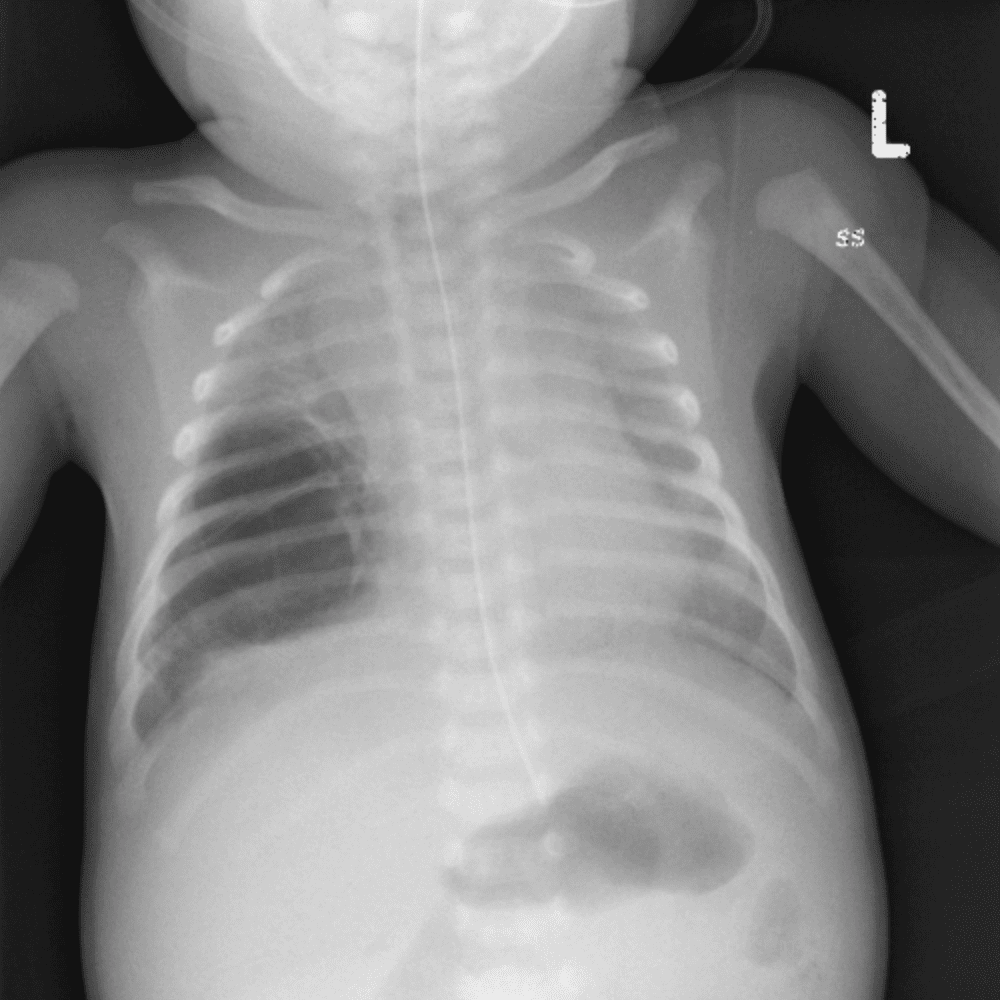

Peds Chest

Practice

Simulates call by including subtle or difficult cases and some normals.

50 cases